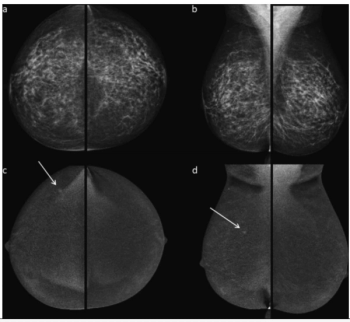

In a 10-year study involving over 5,400 women with nearly 85 percent having dense breasts, contrast-enhanced mammography (CEM) demonstrated a 95.9 percent sensitivity rate for breast cancer.

In a recent interview, Stamatia Destounis, M.D., discussed the impact of national breast density notification for mammography reports and key considerations with staffing and ongoing education for patients, staff and referring providers on the merits of supplemental breast imaging.